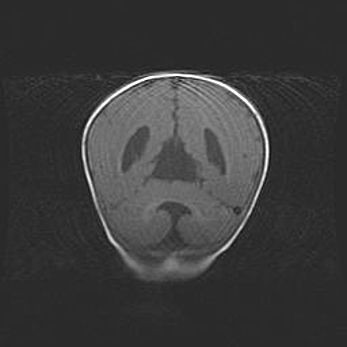

Мальформация Денди-Уокера. Киста задней черепной ямки.

Агенезия мозолистого тела.

Возраст: 2,5 месяца

Вес: 2420 г

Пол: женский

Окружность головы: 37 см

Срок гестации: 32 недели

Мальформация Денди—Уокера — редкий вид патологии ЦНС, представляющий собой врожденный порок развития каудального отдела ствола и червя мозжечка, ведущий к неполному раскрытию срединной (Мажанди) и латеральных (Лушка) апертур IV желудочка мозга. Для этогно синдрома характерна триада симптомов: гипотрофия червя мозжечка и/или полушарий мозжечка, кисты задней черепной ямки, гидроцефалия различной степени. В 70% случаев порок сочетается и с другими аномалиями головного мозга, в частности с агенезией мозолистого тела.